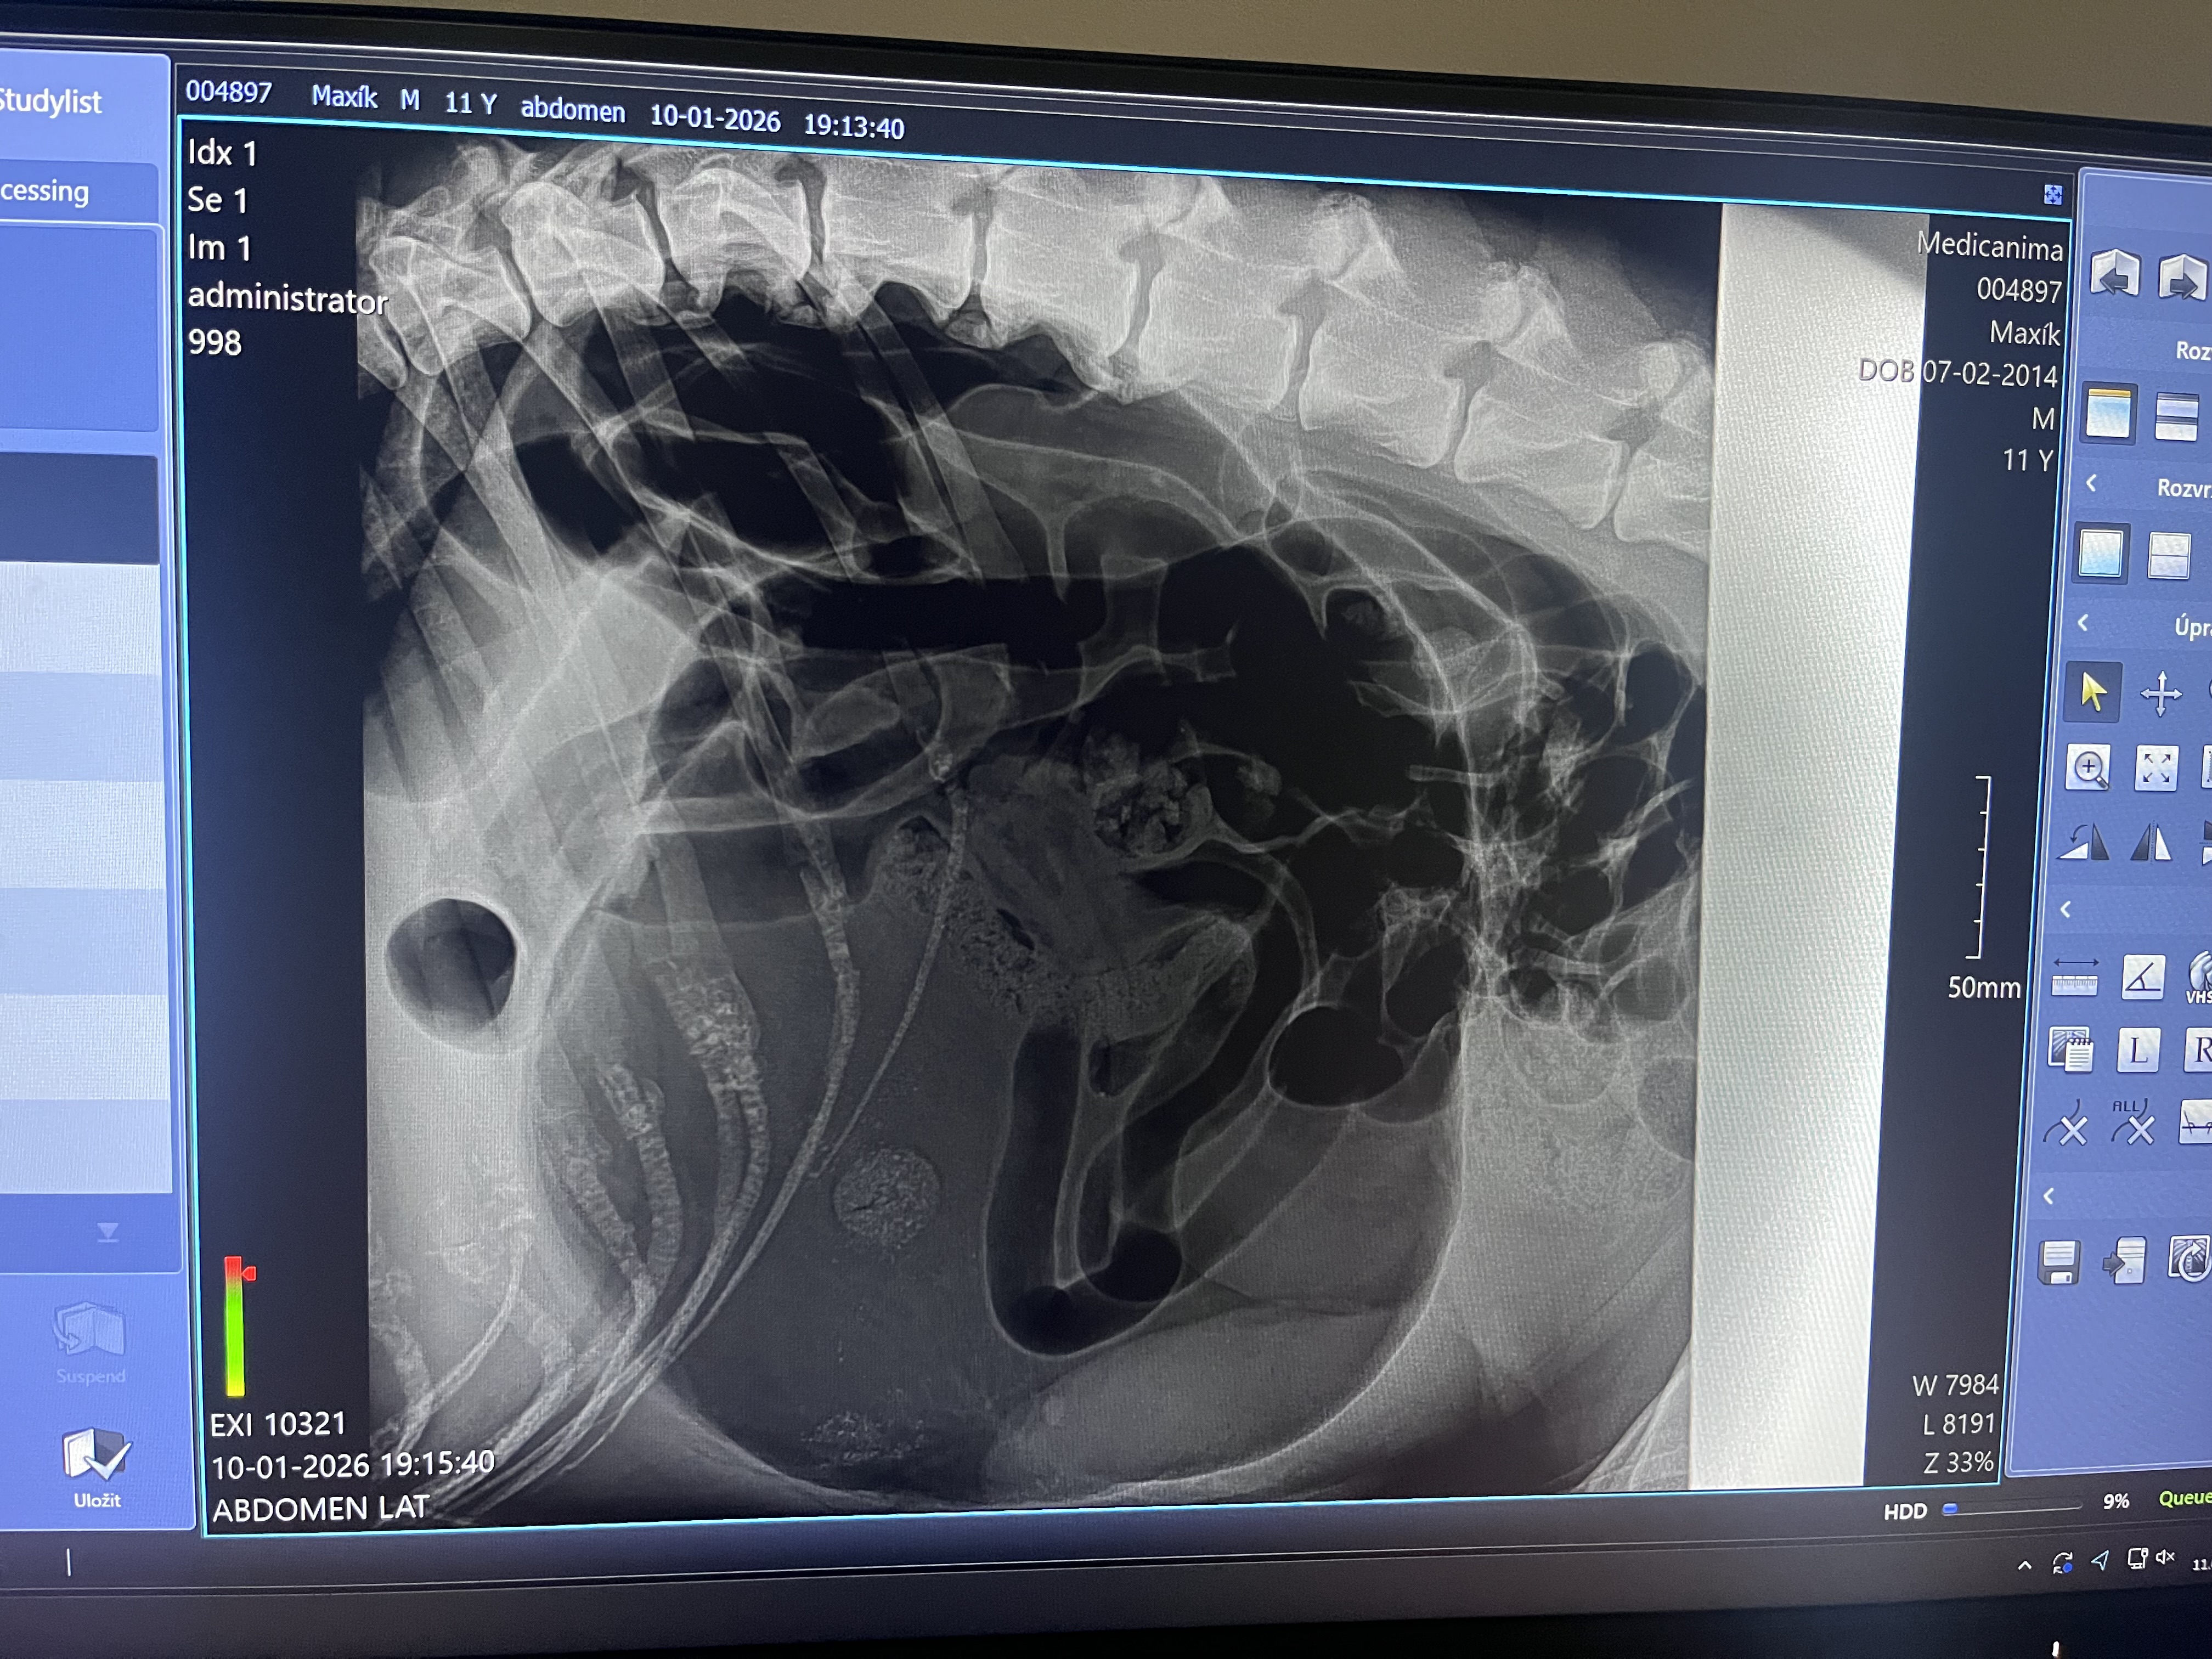

Torze žaludku, odborně Gastric Dilatation and Volvulus (GDV), patří mezi nejzávažnější onemocnění psů. Jedná se o akutní, život ohrožující stav, při kterém se žaludek nejprve naplní plynem nebo potravou (dilatace) a následně se otočí kolem vlastní osy (torze). Tím se uzavře vstup i výstup ze žaludku, naruší se průtok krve, což může vést k rychlému šoku a úhynu zvířete během několika hodin.

Po stabilizaci stavu následuje operace, při které se žaludek:

- uvolní a vyprázdní od plynů a obsahu,

- vrátí do správné polohy,

- a následně se přišije k břišní stěně – gastropexe.